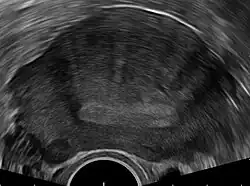

Transvaginal ultrasonography

Transvaginal ultrasonography is a cheap and readily available imaging test that is typically used early during the evaluation of gynecologic symptoms.[24] Ultrasound imaging, like MRI, does not use radiation and is safe for examination of the pelvis and female reproductive organs.[25] Overall, it is estimated that transvaginal ultrasonography has a sensitivity of 79% and specificity of 85% for the detection of adenomyosis.[11]

Common transvaginal ultrasound findings are defined by the European MUSA group in 2015 [26] and are defined in 2022 by the MUSA group.[27] The ultrasound characteristics can be divided in direct and indirect features.

Direct features:

- myometrial cysts - pockets of fluid within the smooth muscle of the uterus

- Hyperechogenic islands - usually white endometrium islands within the myometrium

- Echogenenic subendometrial lines and buds - usually white lines and knobs attached to the endometrium, prtruding into the myometrium.

Indirect features:

- Globular, enlarged, and/or asymmetric uterus

- Fan shaped shadowing - differentiating from fibroids with linear shadowing

- Anterior/posterior wall asymmetry

- Translational vascularity - diffuse spread of small vessels within the myometrium

- Irregular or interrupted junctional zone - the borderline between the endometrium and myometrium

The power Doppler or Doppler ultrasonography function can be used during transvaginal ultrasonography to help differentiate adenomyomas from uterine fibroids.[24][28][29] This is because uterine fibroids typically have blood vessels circling the fibroid's capsule. In contrast, adenomyomas are characterized by widespread blood vessels within the lesion.[24] Doppler ultrasonography also serves to differentiate the static fluid within myometrial cysts from flowing blood within vessels.[24]

The junction zone (JZ), or a small distinct hormone-dependent region at the endometrial-myometrial interface, may be assessed by three-dimensional transvaginal ultrasound (3D TVUS) and MRI. Features of adenomyosis are disruption, thickening, enlargement or invasion of the junctional zone.[21] There is no consensus about the actual histology of the junctional zone and a recent review showed that the ultrasound, MRI and histology all define and describe the junctional zone differently.[30]